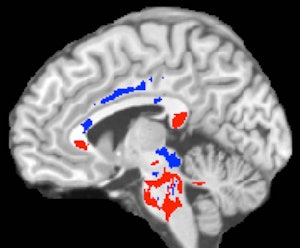

When the concussed patients were compared with the healthy controls, DTI-MRI showed areas of abnormally low fractional anisotropy that correlate with nerve fiber damage and cognitive impairment in concussed patients.

The images also showed other brain areas with abnormally high fractional anisotropy, which may suggest that the brain was responding to the injury by remyelinating, or repairing, injured tissue. Most importantly, having a greater volume of white-matter areas with higher fractional anisotropy correlated with better outcomes and recovery times for concussed patients.

Conversely, the areas of low fractional anisotropy, indicating white-matter damage, were not useful in predicting recovery from concussion one year later.